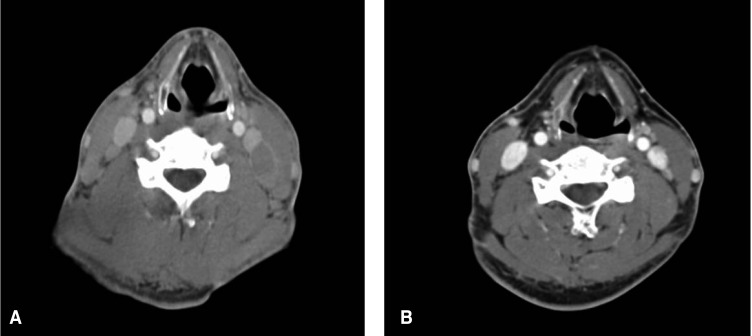

A 38-year-old male with AIDS presented with a palpable mass he'd had for 5 months in the left cervical region. HIV infection was possibly through heterosexual contact and he was diagnosed two years earlier, but no particular treatments were established before admission. On physical examination, 0.8 cm-sized lymph nodes were palpable in the left cervical areas. The heart and lungs were normal, and the chest X-ray was normal. A CT scan of the head and neck (Figure 6A) showed enlarged left sided cervical lymph nodes that measured 1.6 cm × 2.4 cm in diameter. Excisional biopsy of a cervical lymph node was performed, and the histologic study suggested diffuse large B-cell lymphoma (Figure 7A). Immunohistochemical staining showed the atypical cells to be CD20 positive (Figure 7B). On admission, the patient did not declare any discomfort and the physical examination was normal. The laboratory finding were as follows; hemoglobin 14.4 g/dL, WBC 5,310/mm3 (neutrophils: 55.9%, lymphocytes: 39% and monocytes: 4.1%), platelet 178,000/mm3, ESR 9 mm/h, AST 39 IU/L, ALT 32 IU/L, total bilirubin 1.5 mg/dL, LDH 378 IU/L, protein 7.9 g/dL, albumin 4.0 g/dL, BUN 15.9 mg/dL, creatinine 0.88 mg/dL, calcium 8.5 mg/dL, phosphorus 4.2 mg/dL, Na 137 mmol/L, K 4.5 mmol/L, the percent of the CD4 and CD8 T lymphocytes was 20.5% and 70% of the total lymphocyte count, respectively, and the total number of CD4 cells was 420/mm3. The CD4/CD8 ratio was 0.36. He was treated via immunochemotherapy with Rituximab and CHOP for six cycles. After 5 cycle of R-CHOP, the CD4 cell count decreased from 420 to 95/mm3 and a regimen of zidovudine, lamivudine and didanosine were used as HAART. After 6 cycles of R-CHOP, the follow-up CT revealed marked regression in the size of the lymph nodes at both internal jugular channels (Figure 6B). He is currently under follow-up for the lymphoma.

(A) CT scan of the head and neck shows the enlarged left sided cervical lymph nodes that measured 1.6cm × 2.4cm in diameter. (B) After 6 cycles of R-CHOP, the follow-up CT revealed marked regression in the size of lymph nodes in both internal jugular channels.